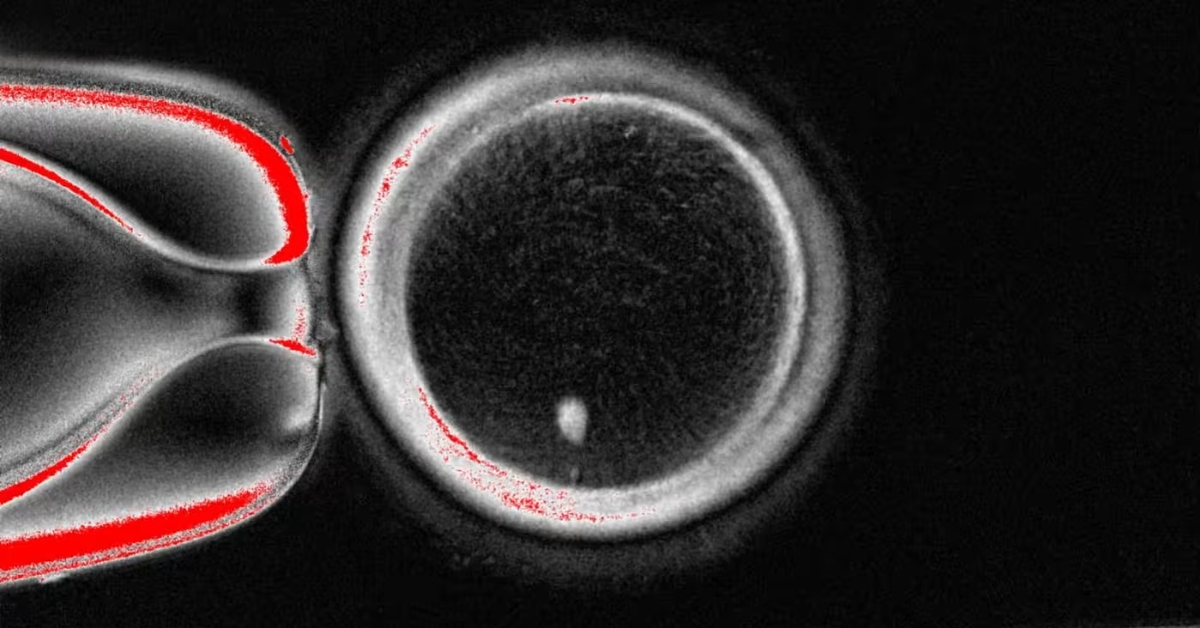

Theo báo Financial Times, quy trình này bao gồm việc chuyển nhân từ tế bào trưởng thành vào trứng đã loại bỏ nhân, sau đó kích thích phân chia để loại bỏ một nửa số nhiễm sắc thể - điều kiện cần cho quá trình thụ tinh.

Trong khi đó, nhóm nghiên cứu đến từ Đại học Y khoa và Khoa học Oregon (OHSU) áp dụng cách chuyển nhân giữa các tế bào trưởng thành. Quy trình này dựa trên một dạng phân bào mới mà họ đặt tên là “mitomeiosis” - sự kết hợp giữa hai cơ chế phân chia tế bào vốn có trong tự nhiên là nguyên phân và giảm phân, giúp tế bào loại bỏ một nửa số nhiễm sắc thể để sẵn sàng cho thụ tinh.

Tuy vậy, hiệu quả vẫn còn hạn chế. Nhóm nghiên cứu ở OHSU đã tạo ra 82 trứng và thụ tinh bằng tinh trùng qua quá trình thụ tinh trong ống nghiệm (IVF) nhưng chỉ 9% phát triển đến giai đoạn phôi nang, trong khi tỉ lệ tự nhiên là khoảng một phần ba.